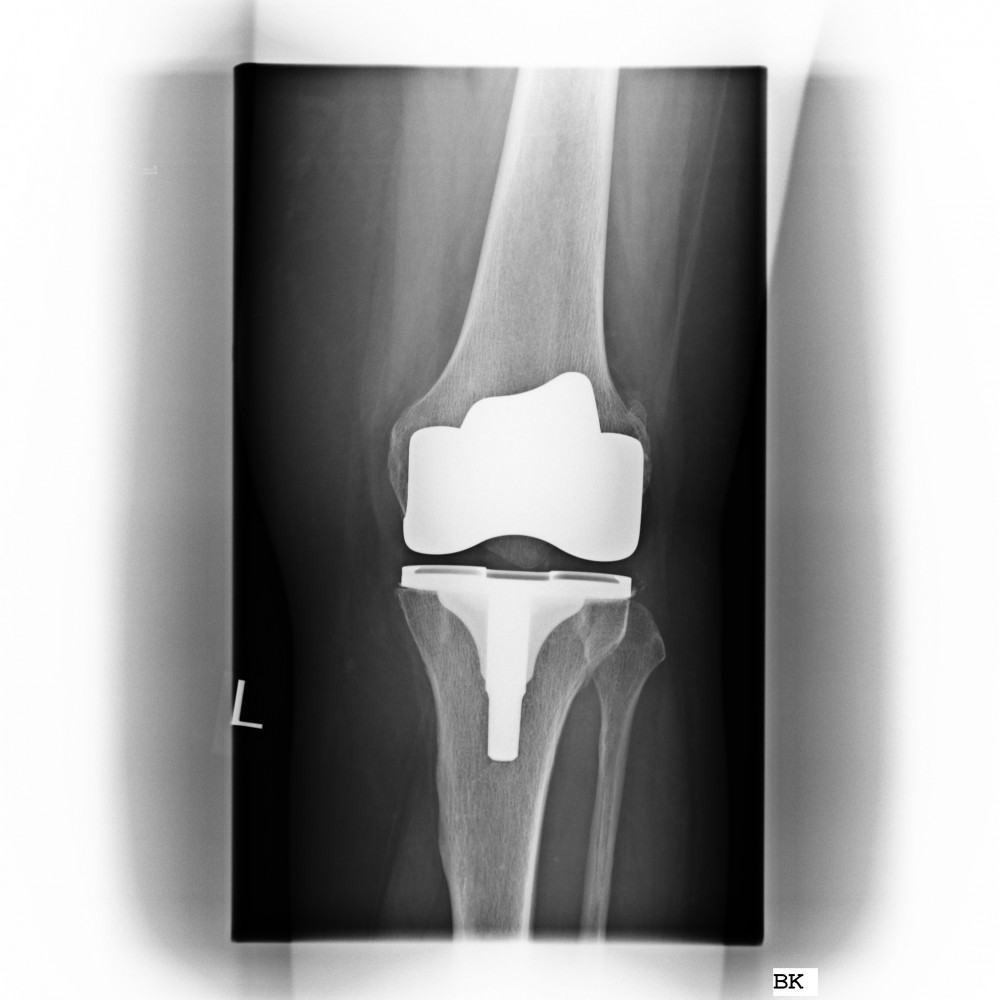

Oberflächenersatz („Knie-TEP“)

Bei einem Verschleiß der gesamten Knorpelfläche bei noch intakten Seitenbändern empfehlen wir einen Oberflächenersatz.

Hierbei werden nur wenigen Millimeter vom Knorpel entfernt um das Implantat passgenau aufzubringen.

Um eine noch höhere Präzision und die bestmögliche individuelle Anpassung des Implantates zu gewähren, bieten wir die Möglichkeit einer individuellen Schnittblockplanung vor der Operation an (Nähere Auskünfte erhalten Sie in der Spezialsprechstunde von Dr. med. Michael Matzer).